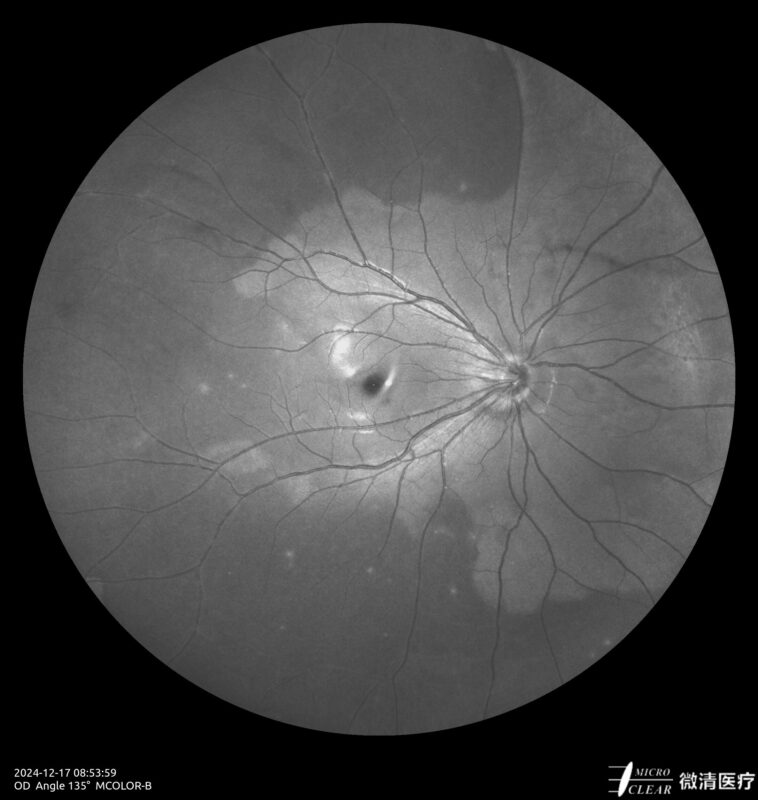

Ultra-groothoek en multimodale fundusangiografie gebaseerd op confocale scanning laser oftalmoscopie (CSLO).

- Blauwe en groene fundusautofluorescentie (Blue AF & Green AF)

- 135° WA (Groothoekangiografie) – in één opname